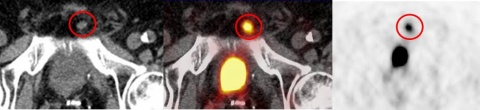

infrapubisch im Nativ-CT (links) mit deutlich erhöhter PSMA-Avidität im PET (rechts)

In einem zweiten Fall konnte ein kleiner, 9 x 8 mm messender Lymphknoten links infrapubisch mit deutlich gesteigerter PSMA–Avidität im PET/CT aufgrund des sogenannten „Halo-Artefaktes“ im PET/MRT nicht verifiziert werden. Der Lymphknoten wies einen erhöhten standardized uptake value (SUV) im PET/CT von 10,1 auf und war somit als eindeutig malignomsuspekt zu werten (Abbildung 4). Im MRT kam der Lymphknoten morphologisch als T2-hyperintens zur Darstellung, zeigte jedoch aufgrund eines ausgedehnten Halo-Effektes keine gesteigerte PSMA–Avidität im PET/MRT (Abbildung 5). In der Literatur wird der „Halo-Artefakt“ als typische Artefaktbildung im PET/MRT, die die Detektion von malignen Läsionen nahe der Harnblase bzw. der Nieren beeinträchtigt, beschrieben [3, 21].

MRT (links, Sequenz: STIR transversal) ohne Nachweis einer gesteigerten PSMA-Avidität im PET (rechts)